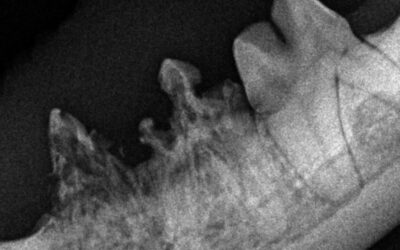

Resorptive Läsionen bei der Katze

Zahnschmerzen auch bei Katzen – was sind die Symptome und wie können diese behandelt werden. Was bedeutet eine Kniescheibenluxation? Wen betrifft es und was kann man machen? Informieren Sie sich hier, wie die minimalinvasive Kastration abläuft und für wenn sich die Methode eignet. Was bedeutet eine Anästhesie und wie sieht der Ablauf aus? Gerne möchten wir Ihnen dieses Thema hier etwas näher bringen. Natürlich putzen Sie sich regelmässig Ihre Zähne. Und Ihr Haustier? Zahnhygiene ist bei Hund und Katze genauso wichtig, wie bei uns. Lesen Sie hier, weshalb und holen Sie sich Tipps und Tricks über die Durchführung. Kastration ja oder nein? Eine viel diskutierte Frage, welche sich nicht allgemein beantworten lässt. Nachfolgend finden Sie unsere Einschätzung dazu.Resorptive Läsionen bei der Katze